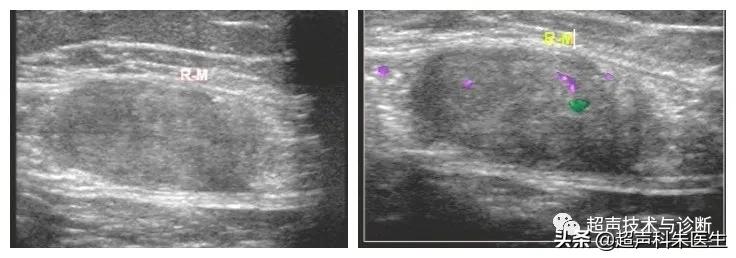

高频探头显示包块内部回声细节

超声所见:下腹部腹膜外探及一低回声团块,大小12.4*6.9*9.0cm,边界清楚,内部回声不均质,内见散在点状强回声及小片状无回声区,包块与腹直肌分界不清,CDFI视察:其内可见少量血流信号。